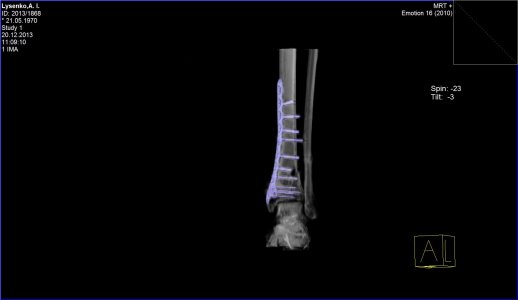

Здравствуйте. Меня зовут Андрей, мне 43 года. 5 сентября этого года меня травмировало на работе - перелом малой и большой берцовой кости со смещением. Операцию сделали 25 сентября, поставили пластину и наложили гипс. Через месяц врач-травмотолог гипс разрешил снять, но сказал, что нагрузку на ногу давать ещё рано. Очередное СКТ, которое я сделал 20 декабря показало, что кость до сих-пор не срослась. В настоящее время я всё-ещё хожу на костылях. Скажите пожалуйста имеет-ли вообще подобный перелом возможность срастись и если да, то сколько времени это может занять. Мой врач ни каких прогнозов дать пока не может и к сожалению ни какой информации мне по этому поводу не дает.